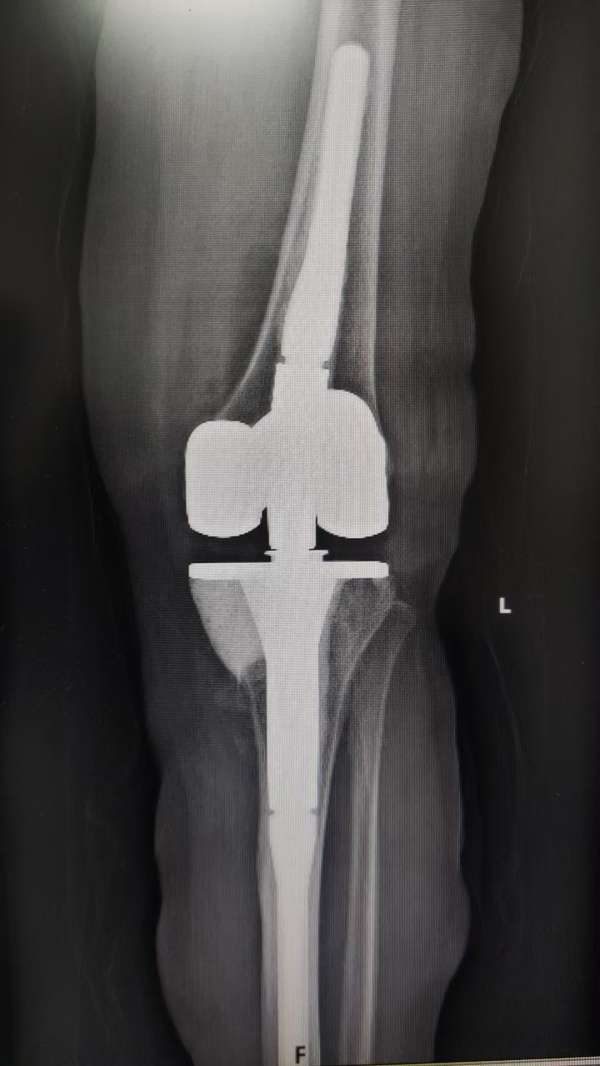

▲术后

术后,在医护团队的精心护理和科学康复指导下,患者恢复良好:膝关节疼痛显著缓解,活动功能稳步恢复。通过定期复查和康复方案调整,其关节功能持续改善,生活质量大幅提升。目前患者康复进程顺利,对治疗效果深感满意,并向医疗团队表达了由衷感谢。